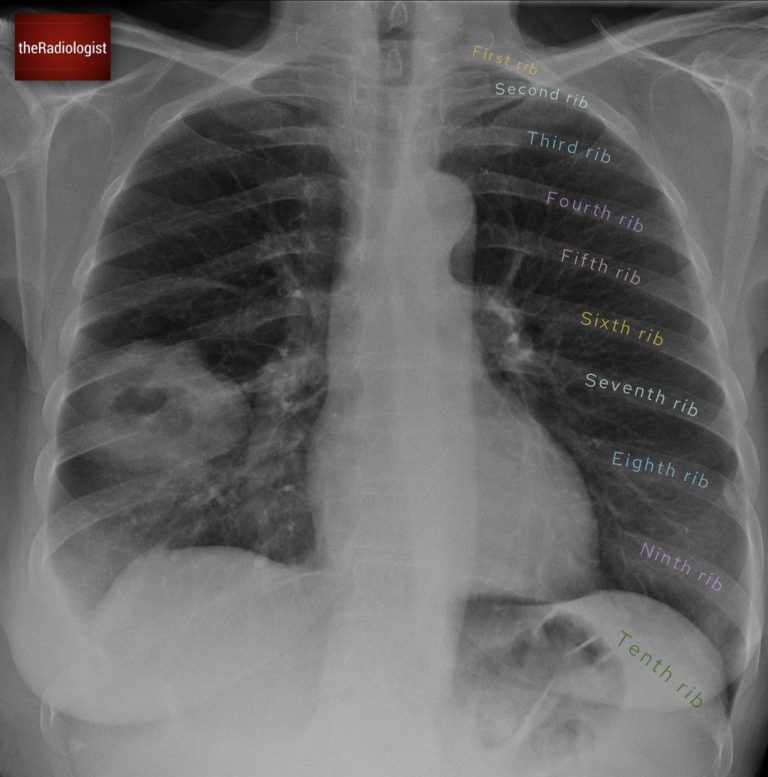

A woman in her 50s went to her GP with right-sided chest pain. Have a look at the initial chest X-Ray below:

PA Chest X-Ray

Examine the chest X-ray systematically and first have a look at all of the ribs on the left.

Firstly outline all of the ribs on the left: no issues here, we can see all of them.

Now have a look on the right, outline all of these ribs and compare with the left. Any problems here?

If you look carefully, you will see the right ninth rib is missing. Now, this is significant. If there’s no history of surgery, the absence of a rib usually means it has been destroyed. And while infections like TB can sometimes cause partial erosion, complete rib destruction almost always points to lung cancer.

This time if you outline the right sided ribs and compare side by side you will find the ninth rib is missing.